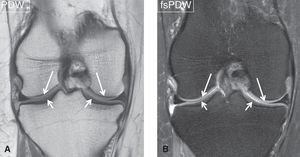

#MR_imaging is the method of choice to identify articular cartilage injuries and evaluate the post-operative reconstitution of cartilage repair tissue. Although various biochemical techniques (such as T2 mapping, T1rho mapping, dGEMRIC, CEST, sodium MRI) are becoming feasible for the assessment of cartilage tissue architecture, conventional morphologic #MRI remains the mainstay for the pre- and post-operative evaluation of the articular cartilage in clinical practice. Most experience and good results in morphological imaging of cartilage and subchondral pathology were gathered with (i) 2D PDW FSE with intermediate TE value (30–60 ms) and high ETL (8-10), (ii) 3D DESS (ideal FA for maximum cartilage signal is 20°-30° and for highest CNR between cartilage and synovial fluid is 90°) and (iii) 3D spoiled gradient-echo (SPGR). Fat suppression in these sequences was found useful to better visualize cartilage pathology, increase CNR and reduce chemical shift artifacts. Coronal images (A, B) of the knee demonstrate a normal articular cartilage (arrows). #MRI #MRI_of_cartilage